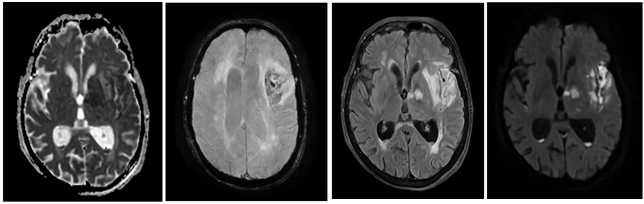

One month after hospital discharge, the patient consulted again due to functional deterioration associated with fever, jaundice, mutism, asthenia, hyporexia and insomnia; Physical examination revealed nuchal rigidity and positive Brudzinski's sign, with lumbar puncture reporting xanthochromic cerebrospinal fluid, with marked pleocytosis at the expense of neutrophils, hyperproteinorrachia and hypoglycorrhachia with glycorrhachia/glycemia index 0.19 (Table 1) and negative meningitis/encephalitis panel. With the diagnosis of meningitis, broad-spectrum antibiotic treatment was started and the patient was transferred to the intensive care unit. A simple cranial tomography was performed, which showed extensive hypodensity in the region of the left middle cerebral artery with vasogenic edema, confirming by contrasted cerebral resonance imaging that it was a vasculitic process associated with neuroinfection (Figure 1).

Figure 1 Brain MRI: axial section at gangliobasal level: (A) Flair, frontoparietal and left-sided internal capsule hyperintensity; (B) SWAN, small areas of hypodensity in relation to hemorrhagic foci in the lesion; (C) ADC, predominant restriction in left internal capsule due to ischemic compromise; (D) DWI hyperintensity in the same region described in the previous image indicating acute lesion.